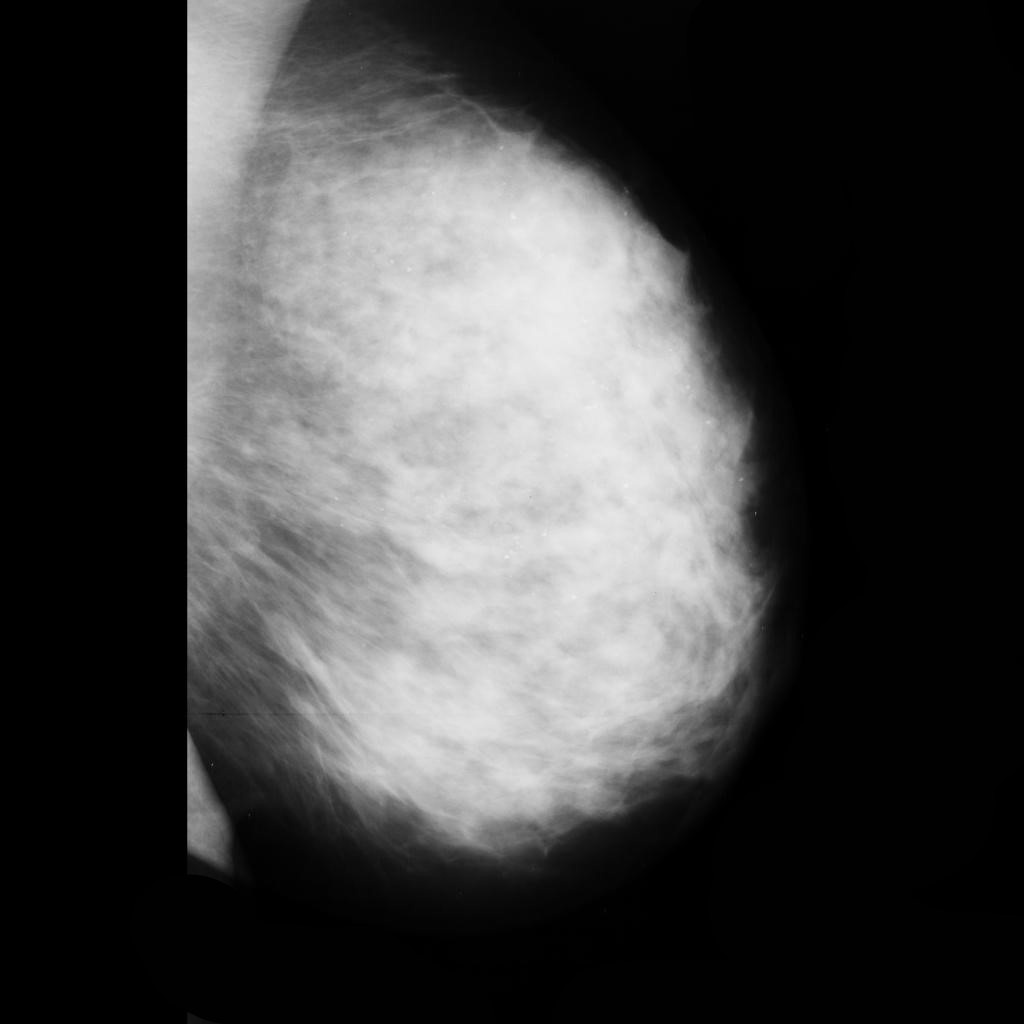

malignant